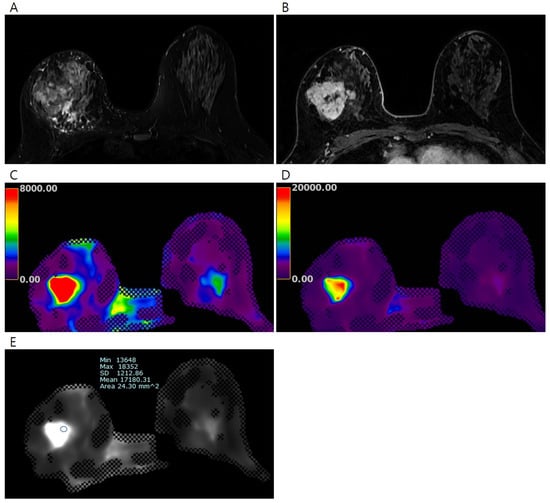

| Variables | All (n = 24) | Non-Pathological Complete Response (n = 18) | Pathological Complete Response (n = 6) | p-Value a |

|---|---|---|---|---|

| Mean elasticity value (kPa) | 10.26 ± 6.84 | 12.20 ± 6.71 | 4.45 ±2.81 | <0.001 |

| Minimum elasticity value (kPa) | 7.01 ± 4.76 | 8.11 ± 4.86 | 3.72 ± 2.55 | 0.047 |

| Maximum elasticity value (kPa) | 14.02 ± 10.75 | 16.97 ±10.79 | 5.19 ± 3.22 | 0.016 |